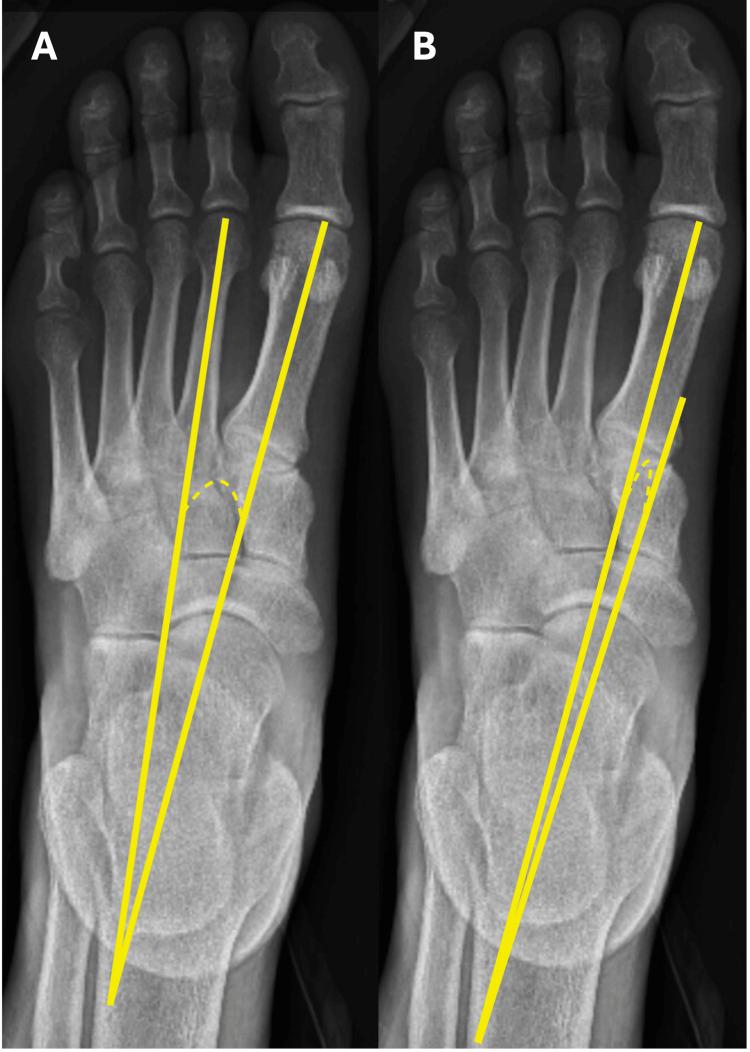

A retrospective review of 440 patients with bilateral foot radiographs was performed. A total of 246 patients met the inclusion criteria. The first to second intermetatarsal angle (IMA), talo-first-metatarsal angle (T1MA), Meary's angle (MA), and calcaneal inclination (CI) were measured. The side-to-side difference and inter-subject variability were analyzed using the mean absolute percentage side-to-side difference (MAPSSD) and the coefficient of variation (COV) to yield the ratio of variation (ROV). An ROV greater than 1 indicates greater inter-subject variability than intra-subject differences. Standard linear model analysis was performed to study each parameter against sex, race, and age. Results: There were no significant differences in IMA, T1MA, or CI in side-by-side measurements, but there was a significant difference in MA between the left and the right side. The ROV for IMA, T1MA, MA, and CI were all greater than 1, indicating greater inter-subject variability than intra-subject variability between the left and the right sides. Male sex was associated with a smaller IMA. Hispanic heritage was associated with smaller T1MA. Older age and Black people were associated with smaller MA angles. Caucasian people had larger CI values. All correlations were statistically significant with a p-value < 0.05.

Intra-subject variability in midfoot anatomy is less than inter-subject variability, therefore validating the use of the contralateral limb as a guide in the surgical repair of midfoot injuries.